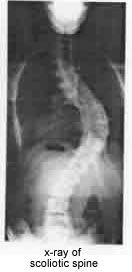

Curvature of the spine, or scoliosis, can be caused by congenital, developmental or degenerative problems. However, at present, the vast majority of cases of scoliosis actually have no known cause.

An 11 hour operation resulted in Sue's back being returned to an "S" instead of a "C" and the rotation from 50 degrees to approximately 14 degrees!!!!!

Scoliosis usually develops in the thoracic spine (upper back) or the thoracolumbar area of the spine, which is between the thoracic spine and lumbar spine (lower back). It may also occur just in the lower back. The curvature of the spine from scoliosis may develop as a single curve (shaped like the letter C) or as two curves (shaped like the letter S).

Xrays